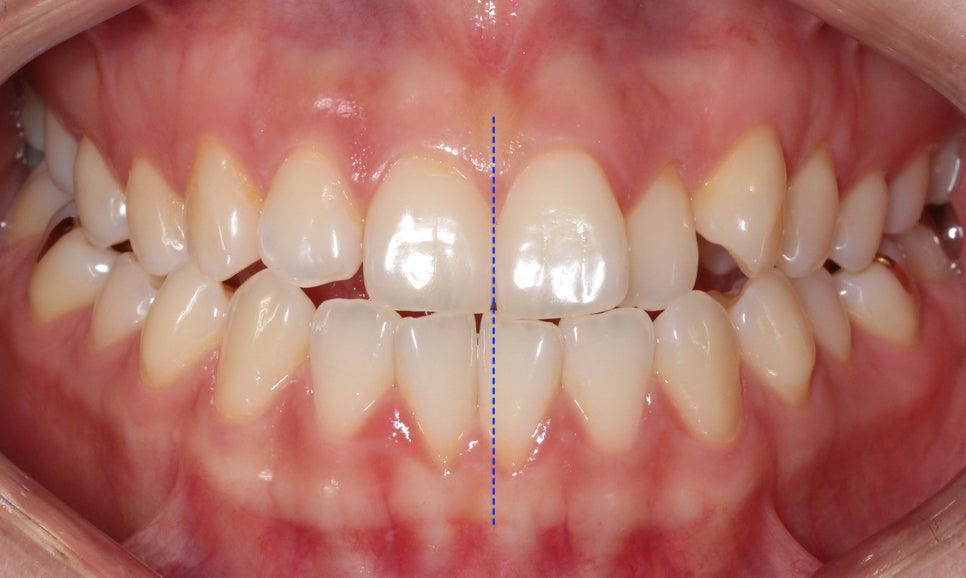

절단교합 교정 전 구내 사진입니다.

전치부를 보면 상악과 하악이

교합되는 부분에서 치아가 맞닿아 있는 모습인데요,

정상적인 교합 상태의 경우 상악이

하악의 윗면을 2mm정도 덮도록 교합됩니다.

(정중선도 변위되어 있는 모습)

증상을 더 자세하게 살펴보면

전치부 overbite 수치가 0에 가까운 모습으로

상악과 하악의 겹쳐지는 부분이 없습니다.